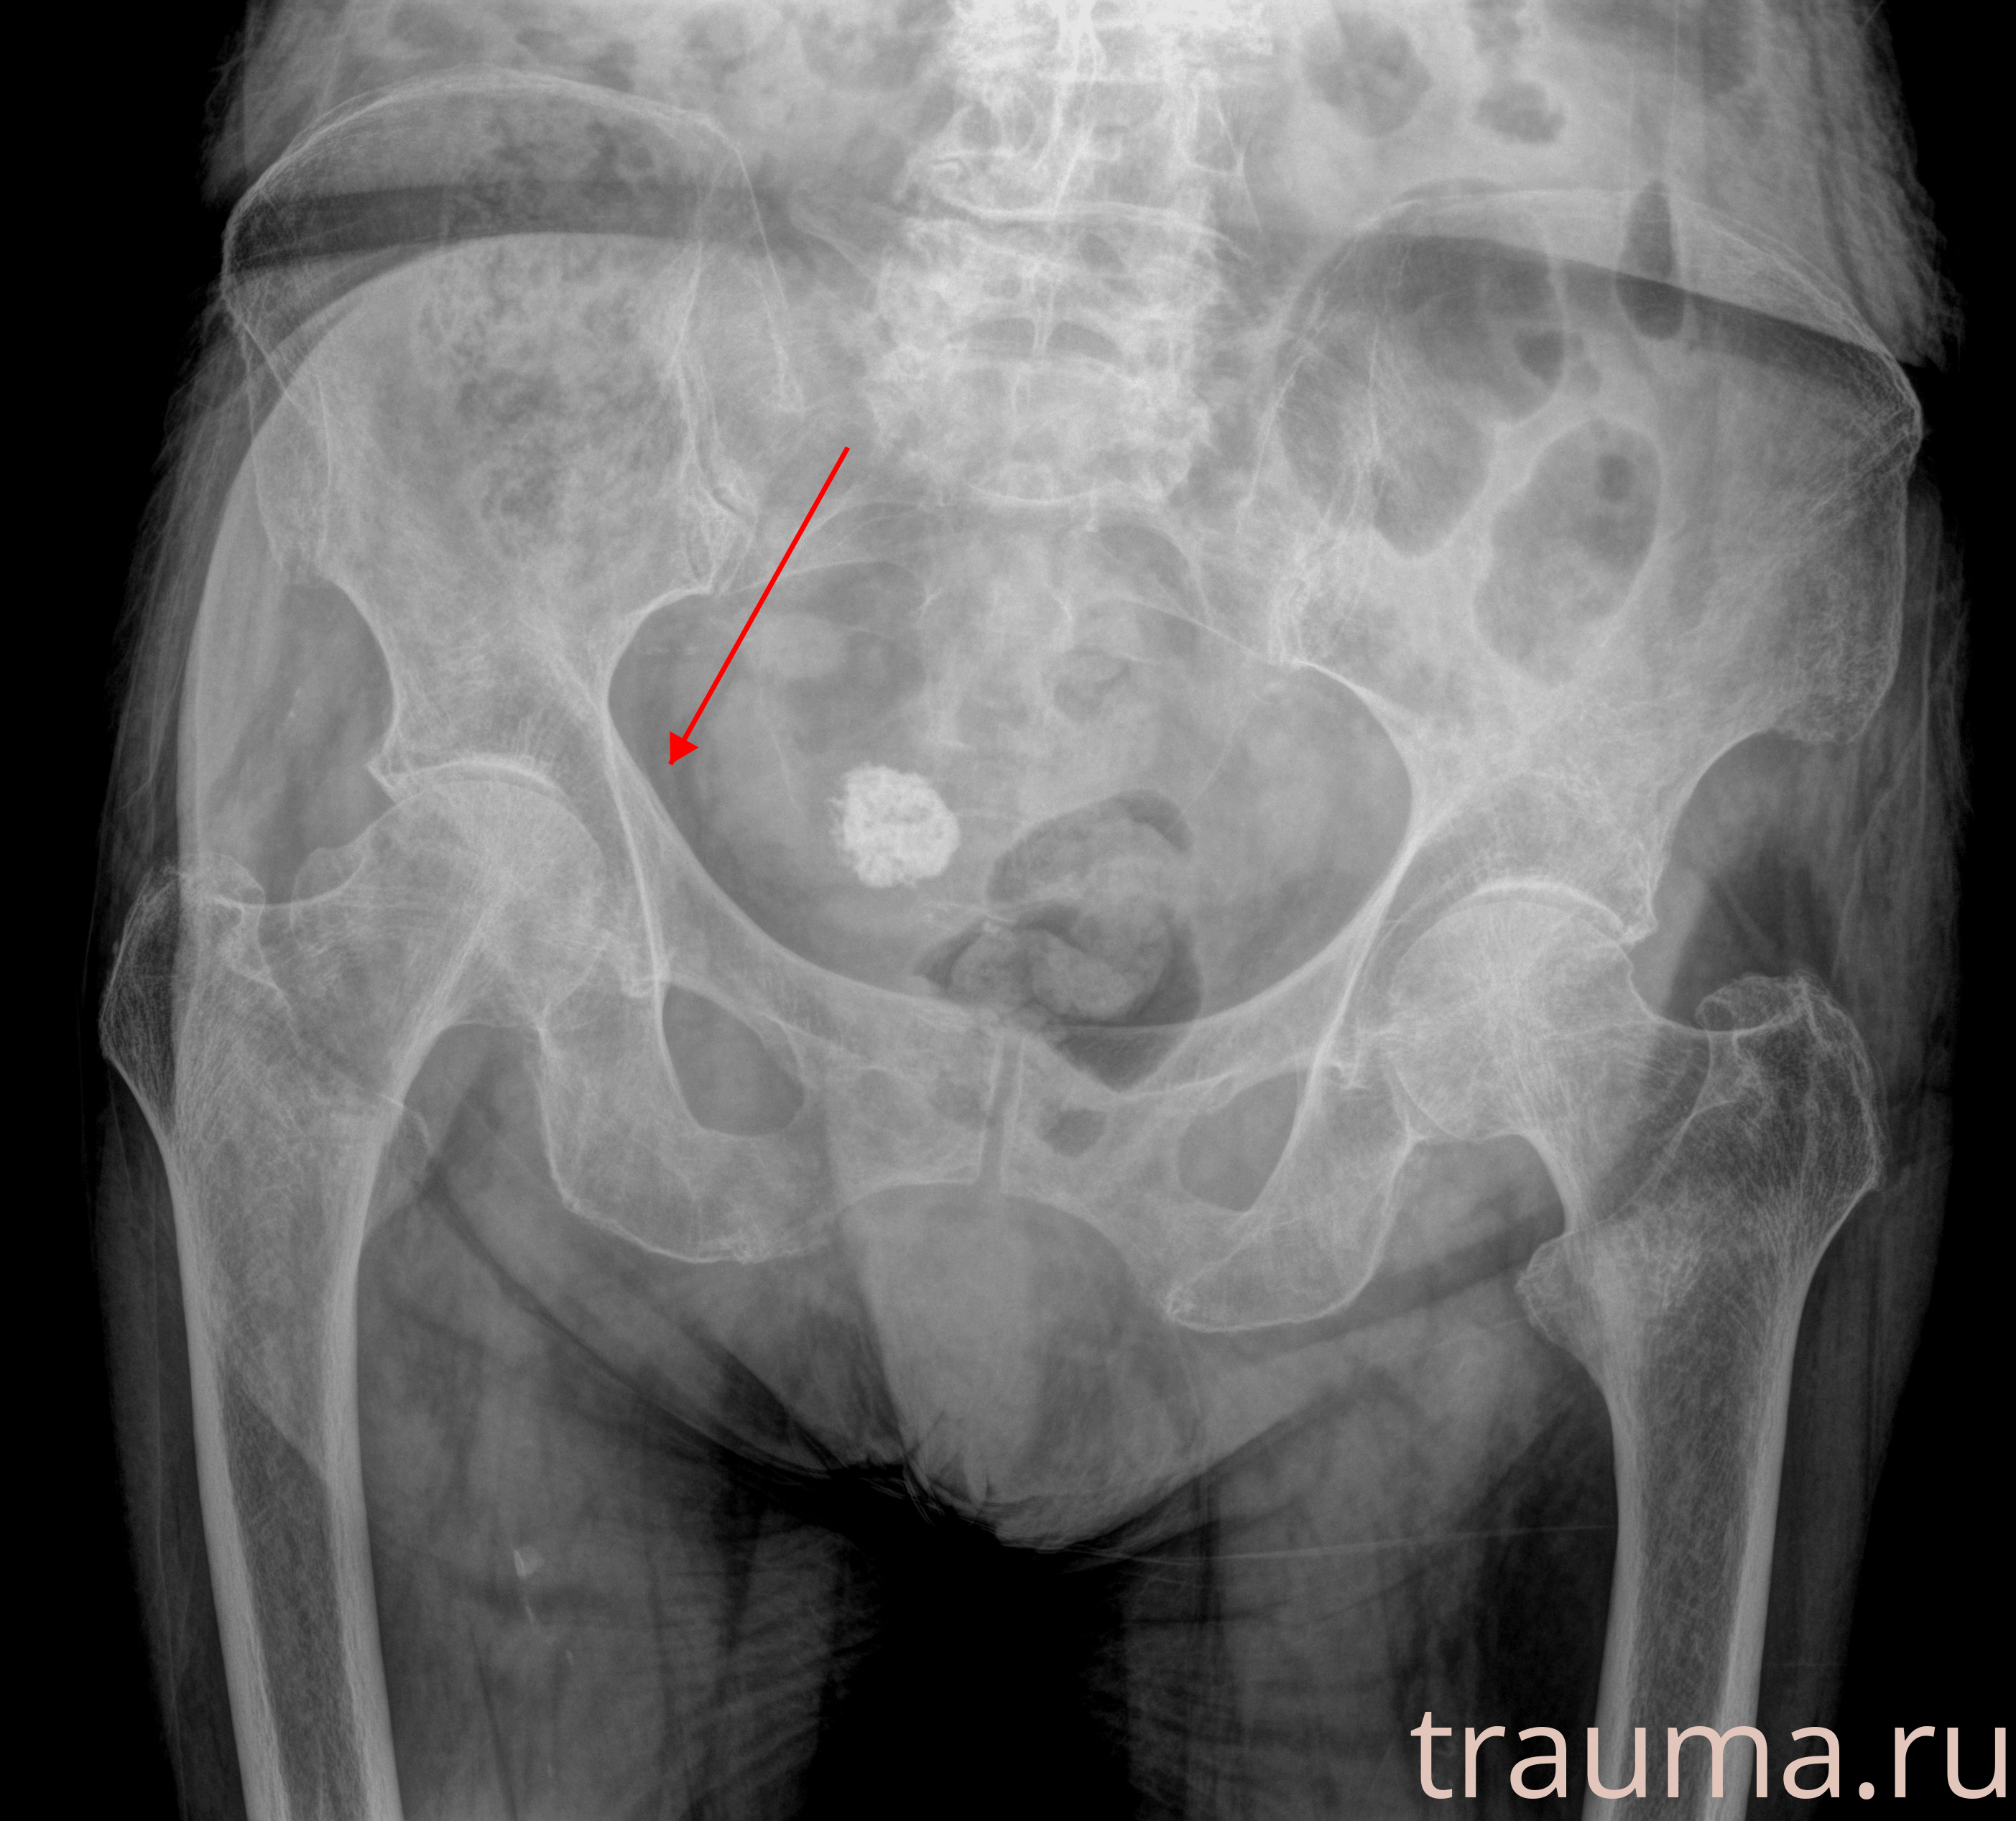

Рентген на дому: по вашему адресу приезжает врач-рентгенолог, травматолог-ортопед с мобильным рентгеновским аппаратом, проводит диагностику травмы или заболевания, делает необходимые рентгенограммы, дает рекомендации по дальнейшему лечению. Получить качественные снимки в домашних условиях возможно благодаря уникальной методике, разработанной МосРентген Центром для института  Склифосовского